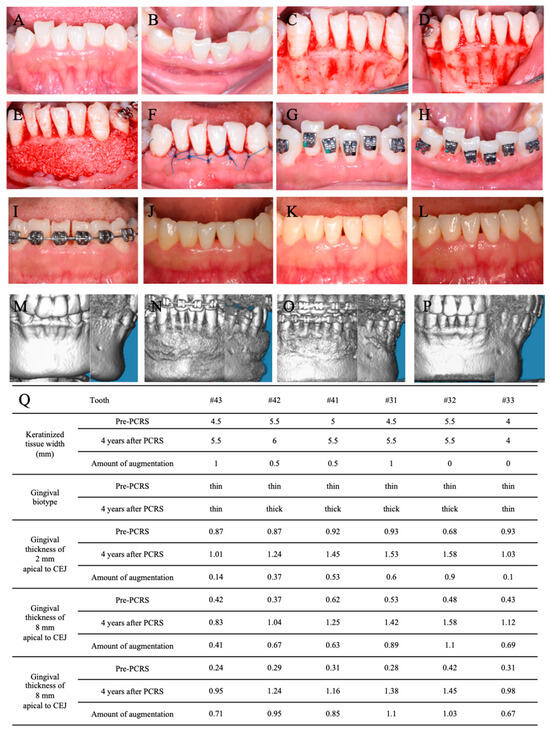

3.3. PCRS with Piezoelectric Devices

3.4. Postoperative Orthodontic Treatment and Maintenance

3.5. Periodontal Maintenance

3.6. Outcome and Follow-Up